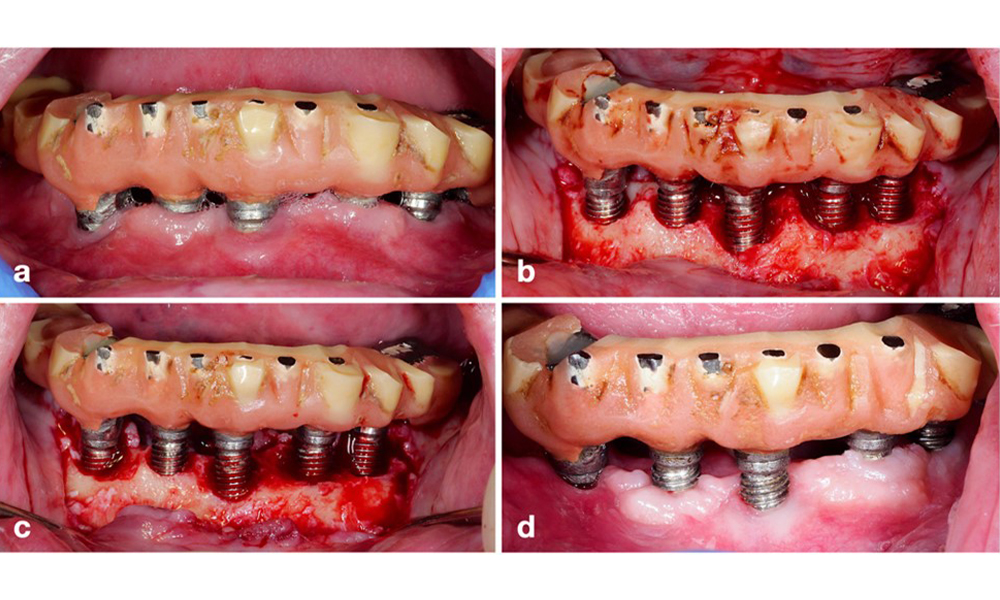

Modification of an existing bridge restoration. If the restoration hinders sufficient oral hygiene measures (notice the extreme overhang on the buccal aspect of the molar) (a–b), one of the first treatment steps should be adjusting the prosthetic design to enable effective cleaning (c–d).

Figure 5. Modification of an existing bridge restoration. If the restoration hinders sufficient oral hygiene measures (notice the extreme overhang on the buccal aspect of the molar) (a–b), one of the first treatment steps should be adjusting the prosthetic design to enable effective cleaning (c–d).